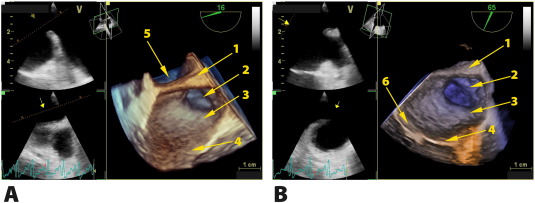

Fig. 1

Fig. 1.

Panel A. TEE: 3D superior view into left atrial cavity and LAA. 1-left lateral ridge, 2-left atrium appendage, 3- baso-medial appendage segment, 4-mitral posterior leaflet, 5-left common pulmonary veins. Panel B. TEE: 3D anterior view into left atrial cavity and LAA. 1-left lateral ridge, 2-left atrium appendage, 3-baso-medial appendage segment, 4-mitral posterior leaflet, 6-mitral anterior leaflet.